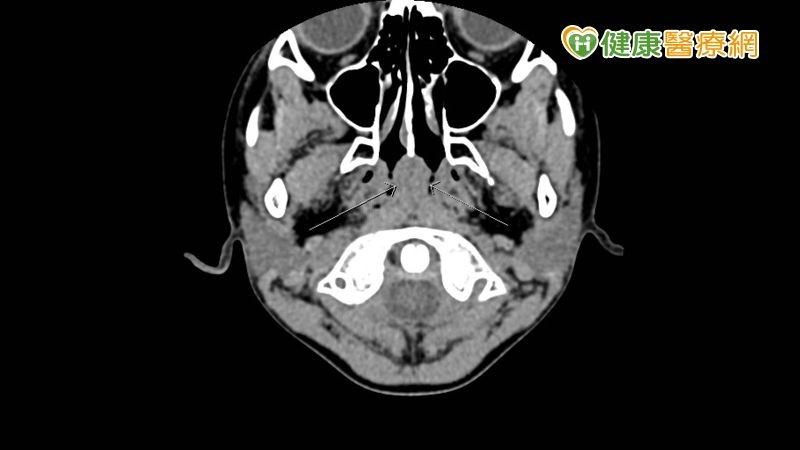

【健康醫療網/記者楊艾庭報導】一名6歲男童,鼻咽部出現腫塊,被誤認為腫瘤,便替他安排頭、頸、胸、腹及骨盆等部位的電腦斷層(CT)檢查,結果在頭頸部發現是正常兒童會有的腺狀體淋巴組織,並非腫瘤,且其餘部位均無異常發現,然而電腦斷層掃描會讓兒童曝露於輻射的疑慮,中華民國放射線醫學會小兒影像診斷次專科委員會召集委員、臺大醫院核子醫學部主任彭信逢醫師表示,根據美國研究指出1,兒童接受電腦斷層檢查,每一次CT掃描,終身約增加0.03-0.05%罹患癌症的風險,且會「逐次累積」,建議若非必要應以其他無輻射的檢查方式替代,如超音波、磁振造影等。

▲6歲男童鼻咽部出現疑似腫塊。